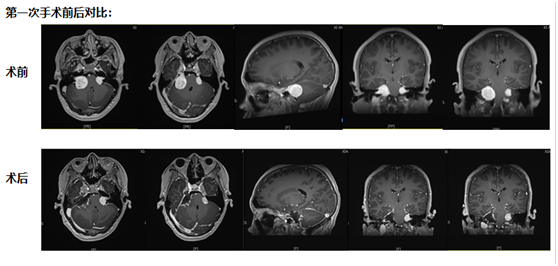

第一次手術:從耳后開口,既要拆瘤又要保聽力

“必須馬上手術!”團隊討論時,周教授分析,“現在腫瘤已經壓到聽力和平衡神經了,再等1個月,負責聽力的神經可能就徹底壞死,到時候再切腫瘤,耳朵也聽不見了。”

考慮到小倪才21歲,團隊沒選 “一刀切” 的方案,而是決定從耳后開一個約10厘米的小口 ——這個位置能精準摸到耳朵旁邊的腫瘤,還能盡量避開控制聽力、面部活動的神經。

手術當天,醫生在顯微鏡下一點點 “剝” 腫瘤:剝到腫瘤深處時,醫生發現再往里切,必然會傷著聽力神經。“停!這里留一點點,先保聽力。”團隊果斷調整,把能安全切除的腫瘤全清干凈,再仔細止血,避免術后出血。